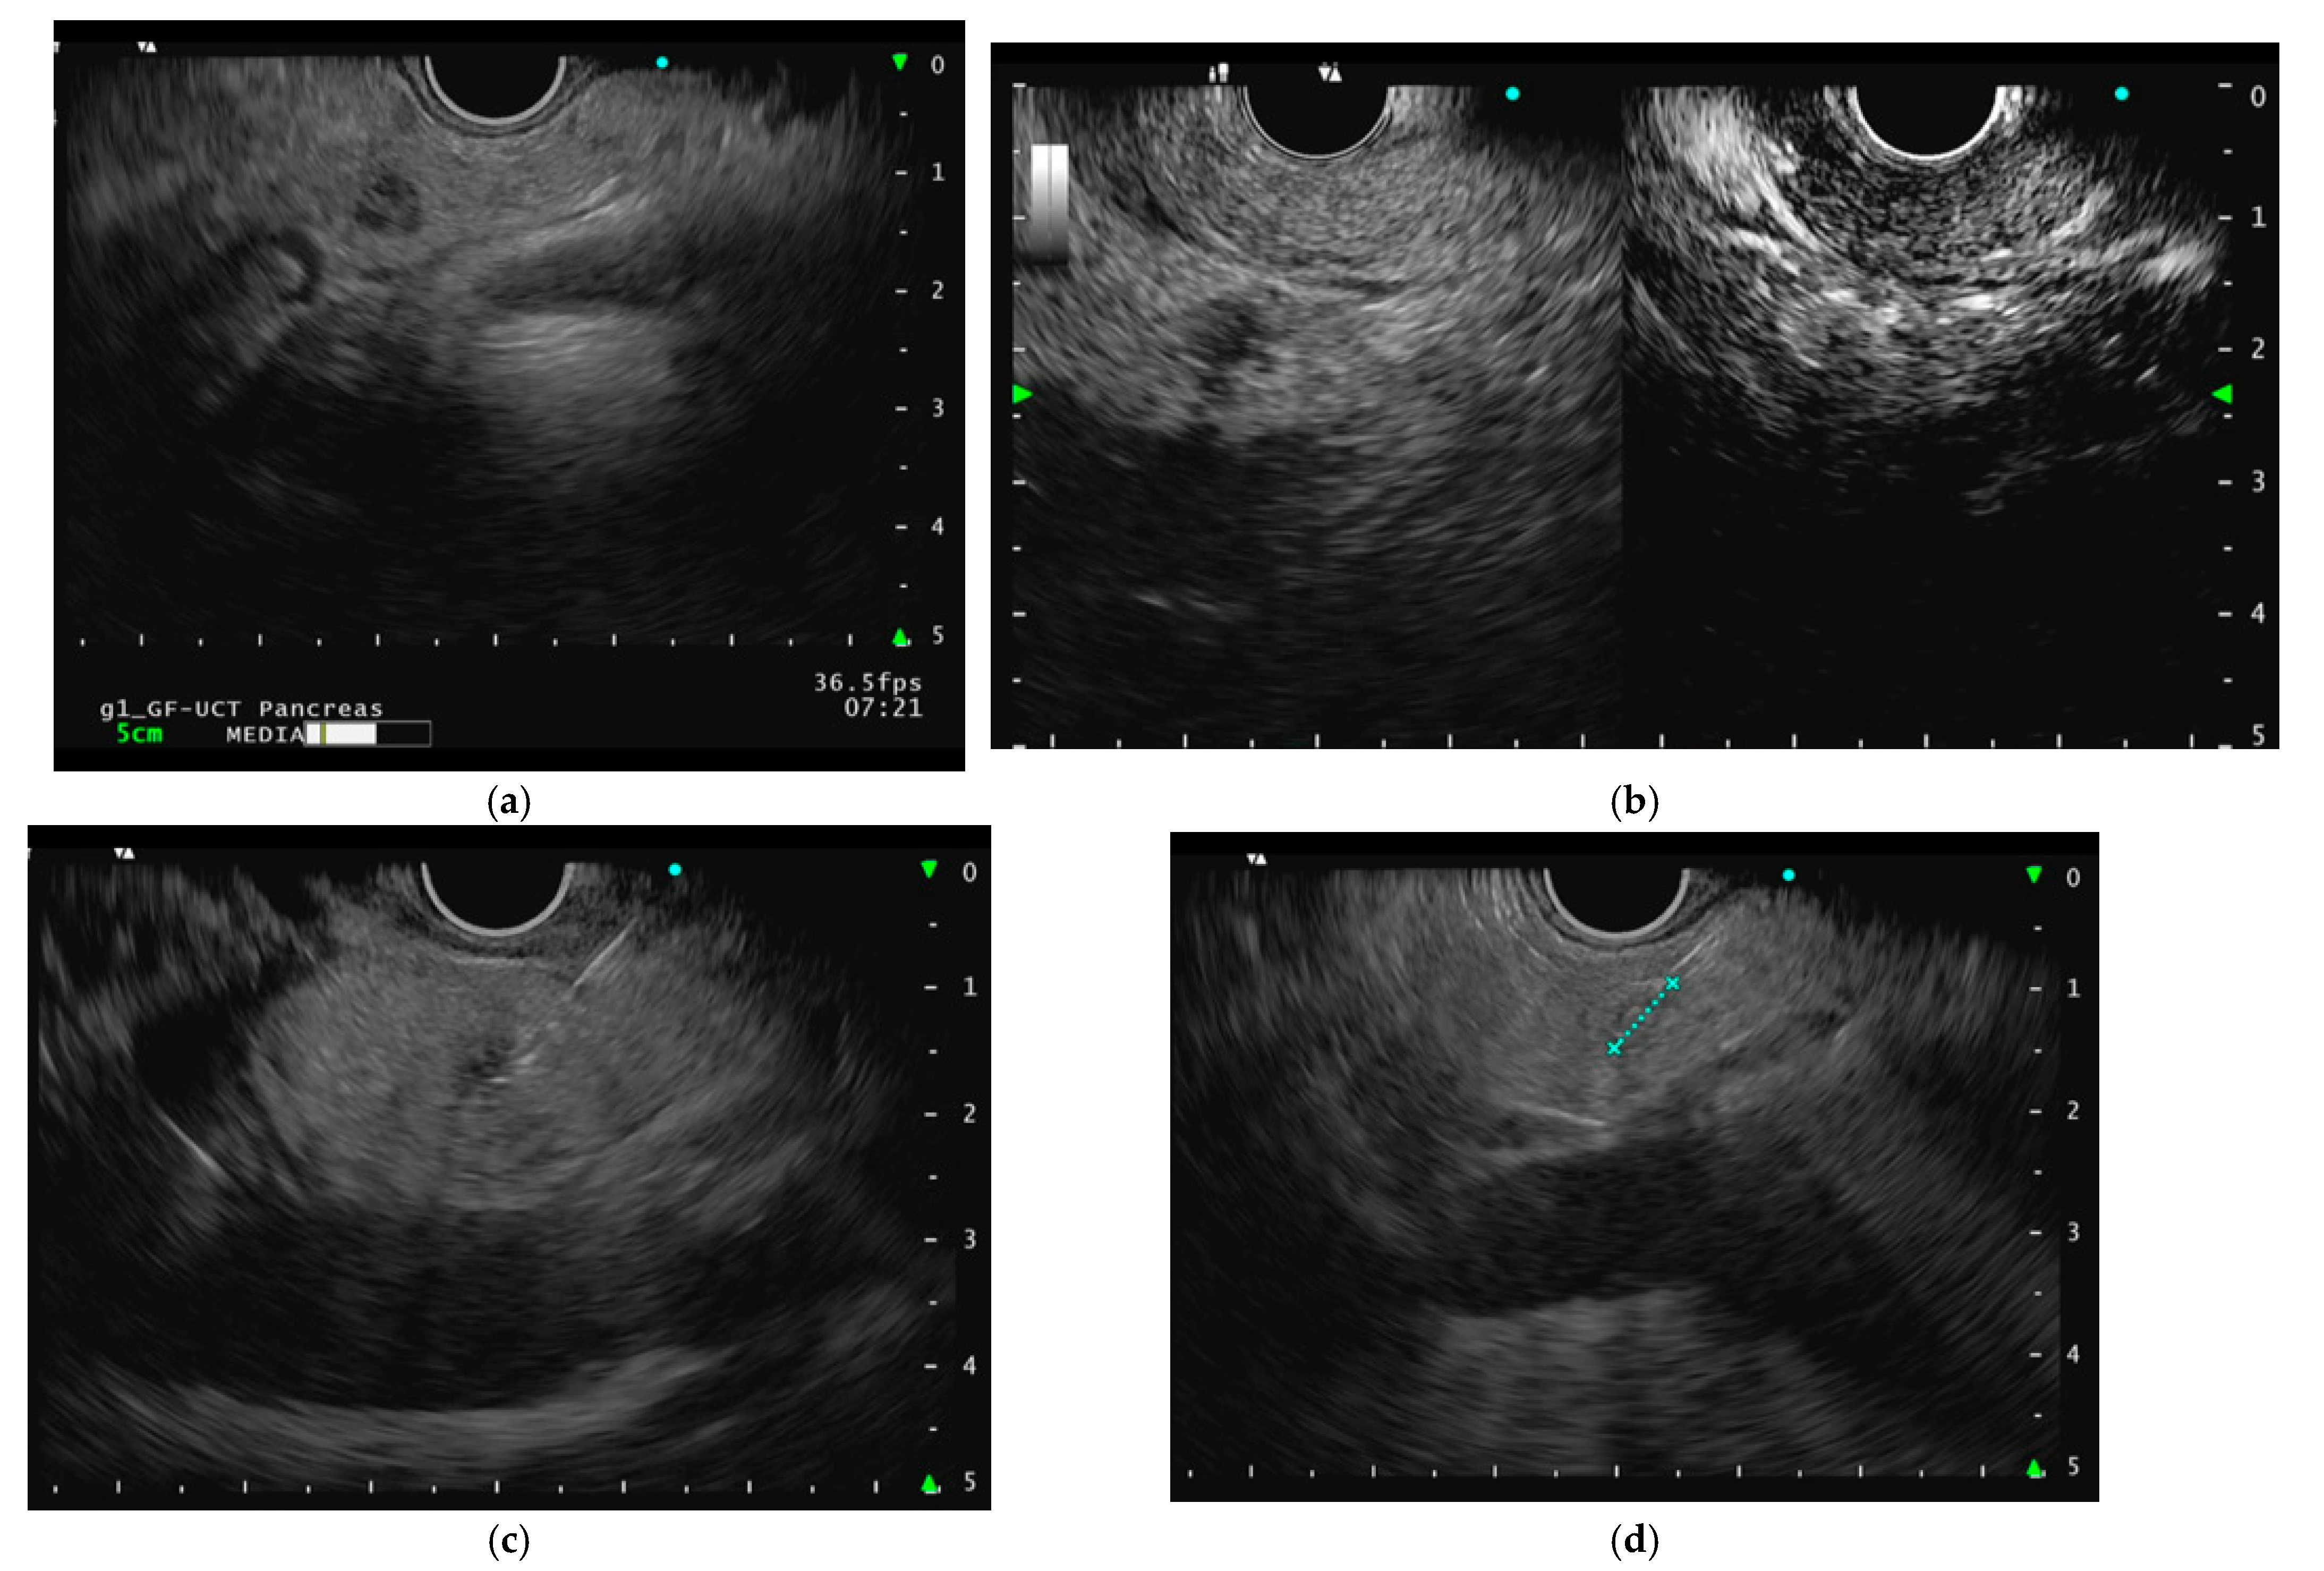

3.1. Procedure

- Choi, J.H.; Seo, D.W.; Song, T.J.; Park, D.H.; Lee, S.S.; Lee, S.K.; Kim, M.H. Utility of Contrast-Enhanced Harmonic Endoscopic Ultrasound for the Guidance and Monitoring of Endoscopic Radiofrequency Ablation. Gut Liver 2020, 14, 826–832. [Google Scholar] [CrossRef] [PubMed]